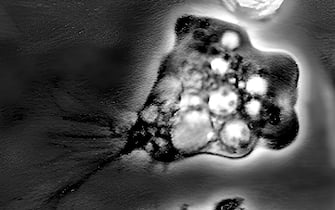

COSA È L’AMEBA MANGIA-CERVELLO

• "La Naegleria fowleri è un'ameba libera termofila che può causare la meningoencefalite amebica primaria (Pam), una condizione rara, ma con esito quasi universalmente fatale”, spiega Miraglia del Giudice. "Questo microorganismo entra nel corpo umano attraverso le narici, tipicamente durante attività che implicano l'immersione della testa in acqua contaminata o i lavaggi nasali con acqua di rubinetto non adeguatamente clorata, e migra al cervello causando gravi danni”